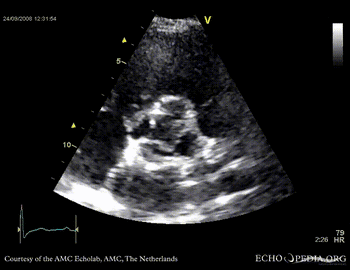

Four leaflet aortic valve

Case description: This patient had four aortic valve leaflets. Two aortic leaflets is a relatively common congenital anomaly. Four aortic valve leaflets is very rarely seen.

PSAX through aortic valve, clearly showing four valve leaflets PSAX through aortic valve, clearly showing four valve leaflets